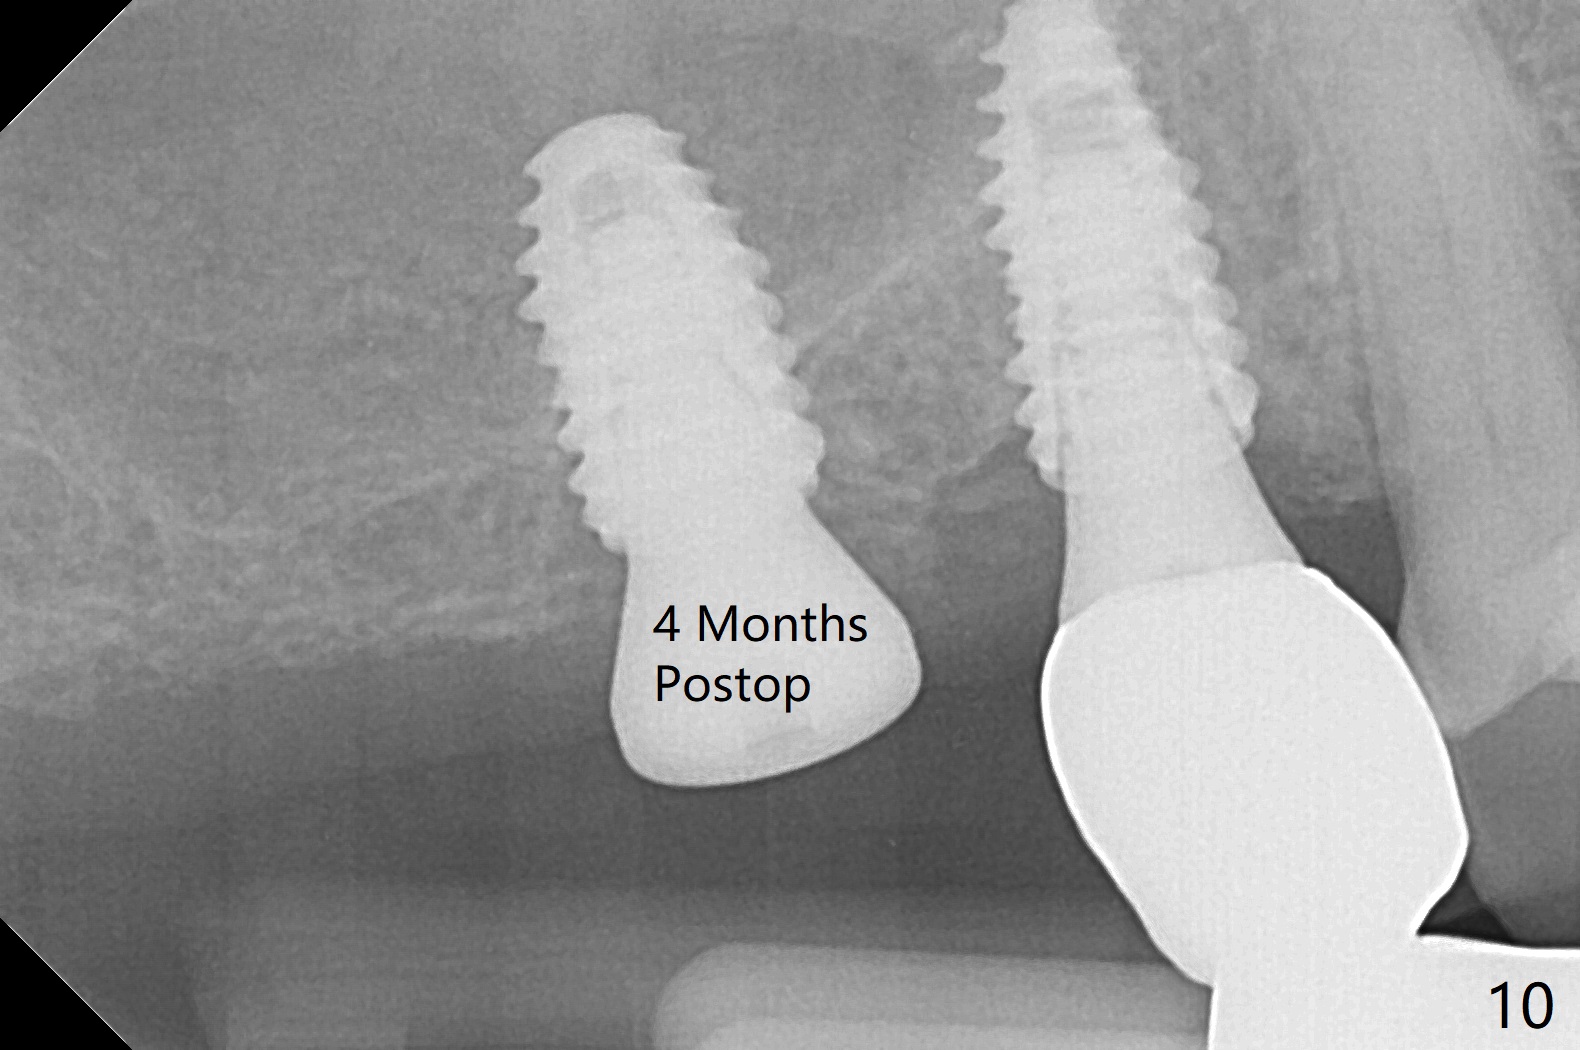

Osteotomy at #3 is performed last (Fig.1,2); as planned, a 4 mm cortical tap is used with guide for sinus lift. Unfortunately the sinus membrane is perforated. Implant placement is aborted. Instead Osteogen plug is inserted into the osteotomy, which is fixed in place by acrylic extending from the provisional at #4. Osteotomy for #3 implant will be attempted with control of the depth in 4 months. The patient has allergy to Amoxicillin (rash). When switching to Clindamycin, she develops diarrhea and loses 10 pounds. There is no abnormality at the site of #3 or 4 nearly 3 months postop (Fig.3). The next surgery will be most likely conducted without antibiotic 4 months postop. Try to draw blood for PRF. Take PA for #12 and 13 for possible impression. Remove the 3 temporary crowns, seat the guide across the arch and use no-stop fixture mounts at #4, and possibly 12 and 13. Follow the original drill sequence (check perforation after each drill, Fig.11) and use DIONavi sinus approach kit. Also load an appropriate stop for the round bur for sinus lift before hand. Mixture allograft with Metronidazole and PRF. In fact everything goes on as smoothly as planned. Osteotomy at #3 is underprep (3.5 mm in diameter drill instead of 4.0). The sinus floor appears to remain to be absent; 3.2 mm round bur is used for lift, alternating with water pumping. Following insertion of 3 pieces of PRF membranes and Vanilla Graft (Fig.4 *), a 4x10 mm dummy implant is placed. After additional bone graft (Fig.5 *), a final 4.5x7.3 mm implant is placed ~10 Ncm. The implant is placed deeper ~ 1 mm, followed by a 5.5x3 mm healing abutment (Fig.6). The implants at #12 and 13 seem to have osteointegrated (Fig.7). Impression is taken for #4, 12 and 13 with limited vertical space (Fig.8,9). An implant at #14 is being considered. There is faint bone graft around the apex of the implant 4 months postop (Fig.10). The implant sustains 25-30 Ncm torque when a 5.2x4(3) mm cemented abutment is placed. A permanent crown is cemented nearly 5 months postop (Fig.11). For the best cosmetic and masticating results, the occlusal surface should have certain degree of morphology, such as the buccal cusps (Fig.12 white curved lines). The abutment at #3 is placed and torqued to 30 Ncm before re-cementation of the repaired crown (increased occlusal surface contact). In fact the abutment at #4 is incompletely seated with a gap (Fig.13 <). The composite at #5 is dislodged while #3 crown is being repaired (*). The abutment at #4 is loose >1 year post cementation. The abutment remains incompletely seated (gap and longer apical space (double arrows)) when the abutment/crown complex rotates lingual mesiobuccal (Fig.14 curved arrow). Further proximal reduction and lingual rotation distobuccal leads to complete seating (Fig.15). It appears that incomplete seating at #13 is associated with hex mismatch (Fig.16, large apical space), which will be fixed next visit. One week later, the crown and abutment of #4 are seated together after crown repair (Fig.17). Since the abutment margin is subgingival, the crown is cemented, removed with abutment for residual cement removal and reseated with the abutment with torque at 30 Ncm. After this, the crown and abutment of #13 is reseated after mesiobuccal surface is trimmed (Fig.18), followed by pick up impression. A few days later, the crown/abutment are inserted together smoothly, the former cemented and the complex unscrewed for residual cement removal and last torqued at 30 Ncm without any X-ray confirmation.